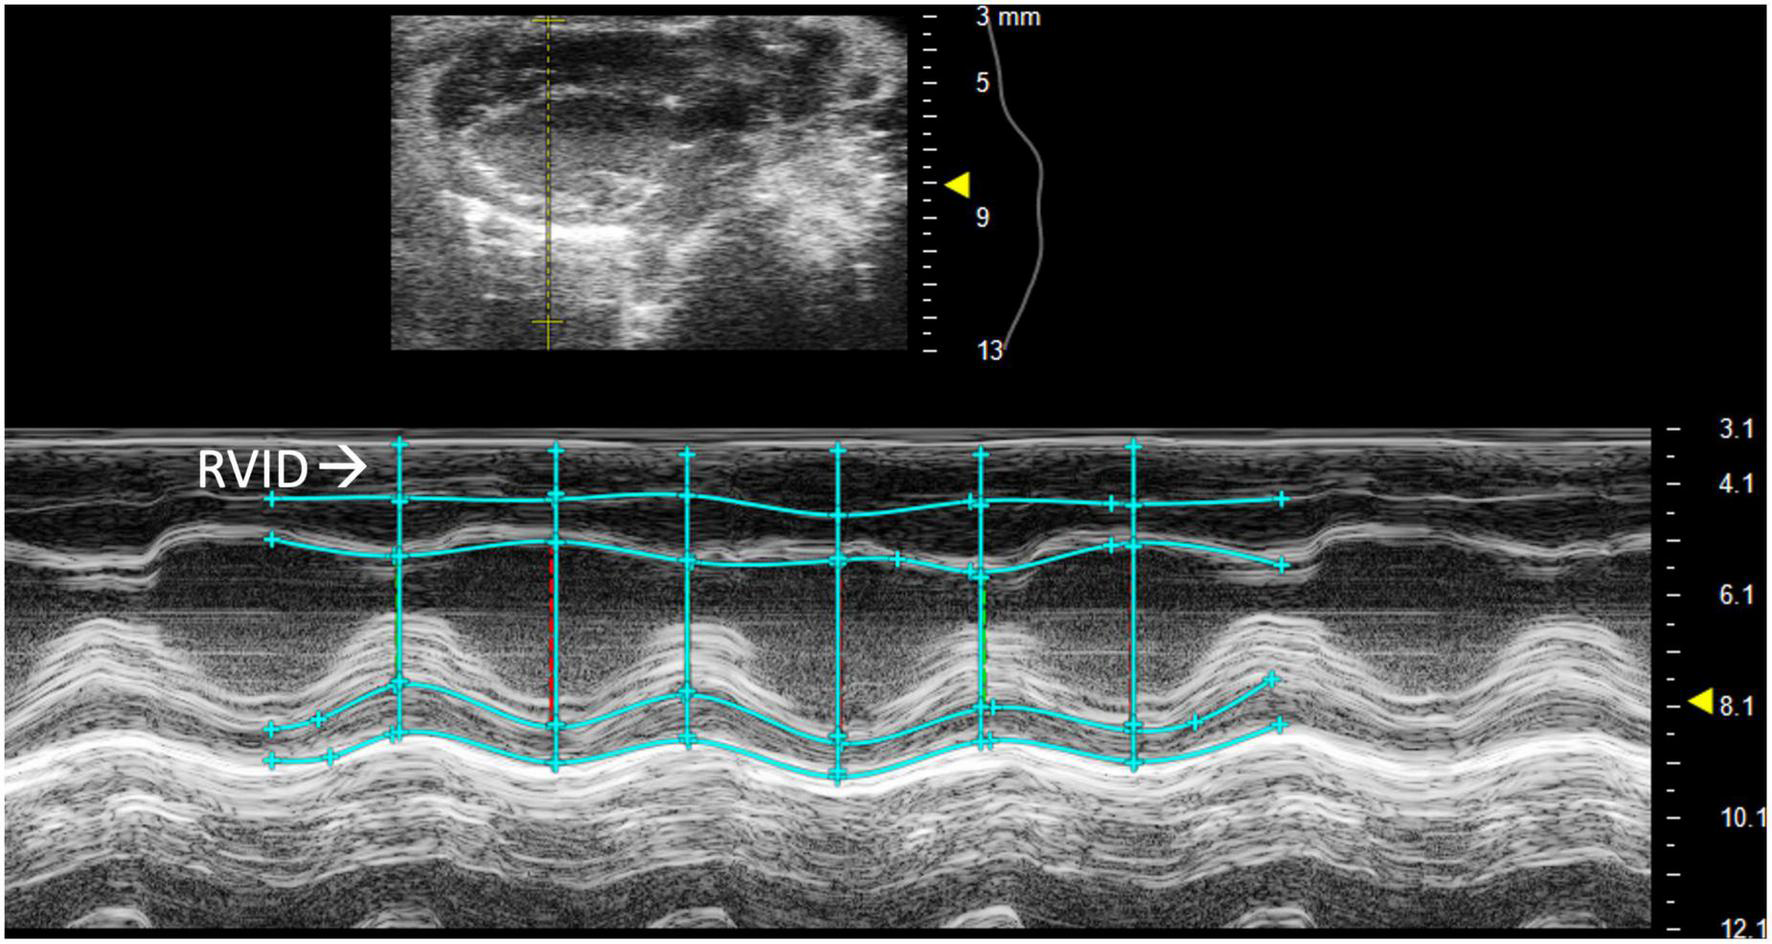

2.2.1.1 Right ventricular internal diameter

Right ventricular internal diameter (RVID) provides metric dimensions of the right ventricle during systole and diastole. To obtain this parameter, a PSAX or PLAX M-mode image should be captured with the M-mode line positioned over the RV. Obtaining the correct view may require repositioning the platform 45° to the right. Furthermore, skin reverberation artifacts can easily be confused with the RV, therefore flow on Doppler or movement in a B-mode image should be used to confirm that the RV is correctly identified. In PSAX or PLAX M-mode, RVID;s and RVID;d should be selected [instead of the intraventricular septum (IVS) IVS;s and IVS;d] to measure the diameter of the right ventricle (Figure 2). This parameter will also measure IVS, left ventricular internal diameter (LVID), and left ventricular pulmonary wall (LVPW). Increased RVID would be indicative of right ventricular dilation or volume overload and thus useful to evaluate RHF.

FIGURE 2

Right ventricular internal diameter (RVID), a measurement of the right ventricle during systole and diastole, is obtained by analyzing parasternal long axis (PLAX) view images in M-mode.